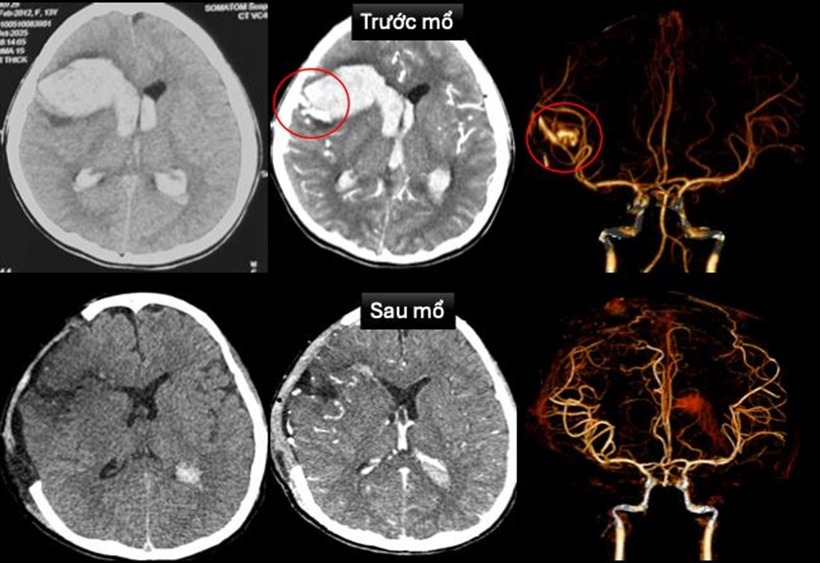

Tại Khoa Cấp cứu, bệnh nhi được ghi nhận hôn mê sâu, thở máy qua nội khí quản, nhịp tim chậm, huyết áp thấp và phải duy trì thuốc vận mạch. Các bác sĩ nhanh chóng tiến hành siêu âm tim, chụp cắt lớp vi tính sọ não dựng hình mạch máu não để chẩn đoán. Kết quả xác định em bị dị dạng động tĩnh mạch trán phải vỡ gây xuất huyết nhu mô não lan vào hệ thống não thất, kèm theo sốc tim, rối loạn nhịp và bệnh cơ tim xốp.

Sau khi hội chẩn đa chuyên khoa, ê-kíp khẩn trương can thiệp cấp cứu. Bác sĩ tim mạch can thiệp đặt máy tạo nhịp tạm thời, đồng thời bác sĩ ngoại thần kinh thực hiện phẫu thuật cấp cứu mở sọ giải áp, vi phẫu cắt dị dạng mạch máu não và lấy máu tụ trong nhu mô não cùng não thất.

Hình ảnh chụp cắt lớp vi tính sọ não và dựng hình mạch máu não trước mổ và sau mổ. Ảnh: VietNamNet.

Sau mổ, bệnh nhi được chuyển Khoa Hồi sức Ngoại để điều trị hồi sức tích cực, thông khí cơ học, sử dụng thuốc vận mạch và chống phù não. Hiện em T. đã tỉnh táo, chỉ còn yếu nhẹ chân phải. Tình trạng tim mạch ổn định, đã rút được máy tạo nhịp và ngưng thuốc vận mạch. Hình ảnh chụp cắt lớp vi tính sọ não sau mổ không còn ghi nhận dị dạng mạch máu não. Siêu âm tim kiểm tra cho thấy bệnh cơ tim xốp với chức năng co bóp cơ tim cải thiện (EF 65%).